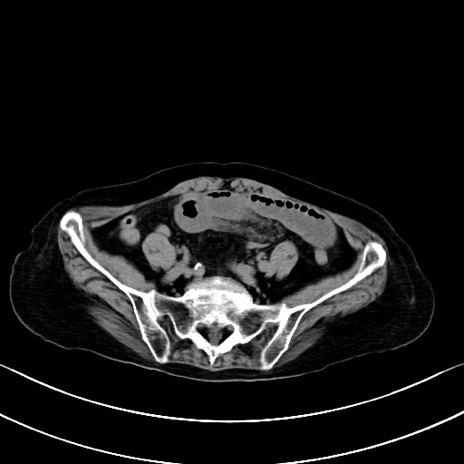

横断像

他院CT